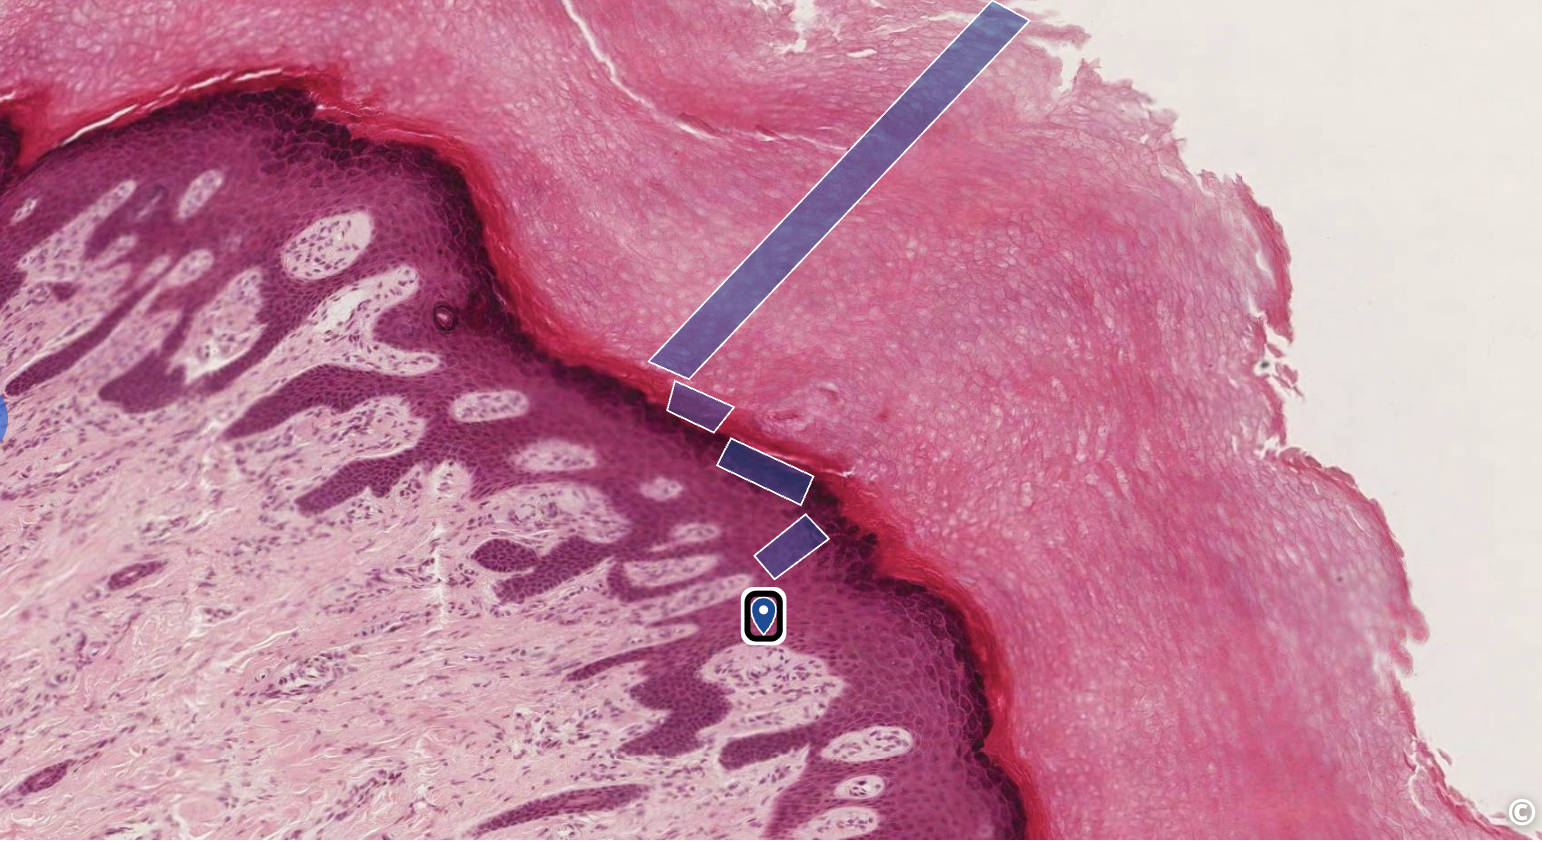

<p>label the layers of the integument</p>

label the layers of the integument

epidermis, dermis (papillary layer, reticular layer), hypodermis

<p>identify all layers of thick skin</p>

identify all layers of thick skin

stratum corneum, stratum lucidum, stratum granulosum, stratum spinosum, stratum basale

<p>identify all layers of thin skin</p>

identify all layers of thin skin

stratum corneum, stratum granulosum, stratum spinosum, stratum basale

<p>identify the layers of the dermis</p>

identify the layers of the dermis

papillary layer (loose areolar CT), reticular layer (dense irregular)